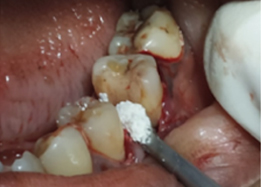

Bone Graft Placement

Hemisectomy

Placement of PRF Membrane